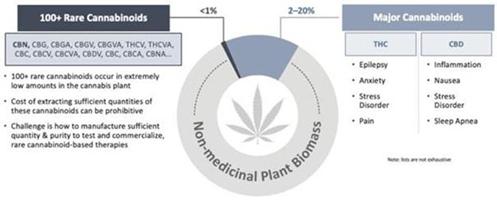

Cannabinoid Science Overview

Cannabinoids are a class of compounds that exist throughout nature and can be found in significant numbers and varying quantities in the Cannabis plant. The two predominant, or major, cannabinoids in the Cannabis plant are THC and CBD. These two exist in relatively large quantities in the plant and can be easily extracted, which has led to significant research into these two compounds over the previous several decades. Nevertheless, there are over 100 additional cannabinoid compounds found in the plant, referred to as minor or rare cannabinoids. Each cannabinoid has one or more specific chemical differences that may confer unique physiological properties in humans.

Rationale for Use of CBN in Pharmaceutical Drug Development

CBN is one of several rare cannabinoids naturally produced in the Cannabis plant, albeit at significantly lower levels relative to the more commonly known THC and CBD. Despite their common origin, different cannabinoids have been observed to have distinct physiological properties, we are specifically exploring these unique effects of CBN, as well as other rare cannabinoids, and their therapeutic potential to treat disease.

Rare vs. Major Cannabinoids: Types, Prevalence & Application

Our extensive preclinical testing has identified several unique properties of CBN that outperformed both THC and CBD in various disease-related assays and models. CBN can act with higher potency when interacting with some receptor systems in the body, while acting with lower potency for others.

While there are over 100 different individual cannabinoids in the Cannabis plant, the two most well-known and studied compounds are also the two that occur in the largest quantities: THC and CBD. Due to their relative abundance in the Cannabis plant, it is also only THC and CBD that can currently be extracted economically. Among other challenges, the expense of extraction – or that of synthetic manufacturing – of the remaining minor or rare cannabinoids, may be orders of magnitude greater than that of THC and CBD.